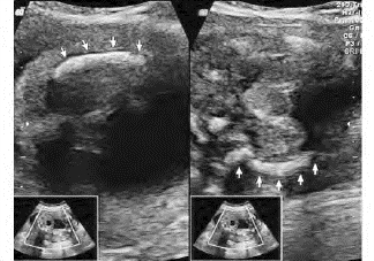

1.38.12十二、胎儿畸形

1.38.13十三、羊水过多和过少